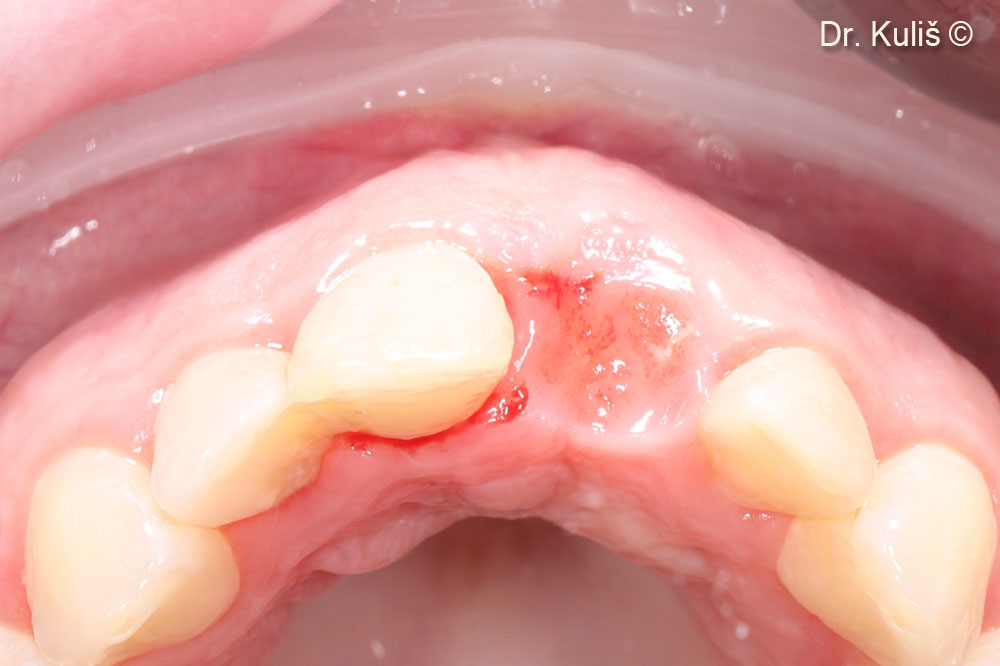

Một bệnh nhân nữ (33 tuổi) có tổn thương quanh chóp răng cửa giữa bên phải.

Tình trạng ban đầu. Dịch mủ do tổn thương quanh chóp răng cửa giữa bên phải.